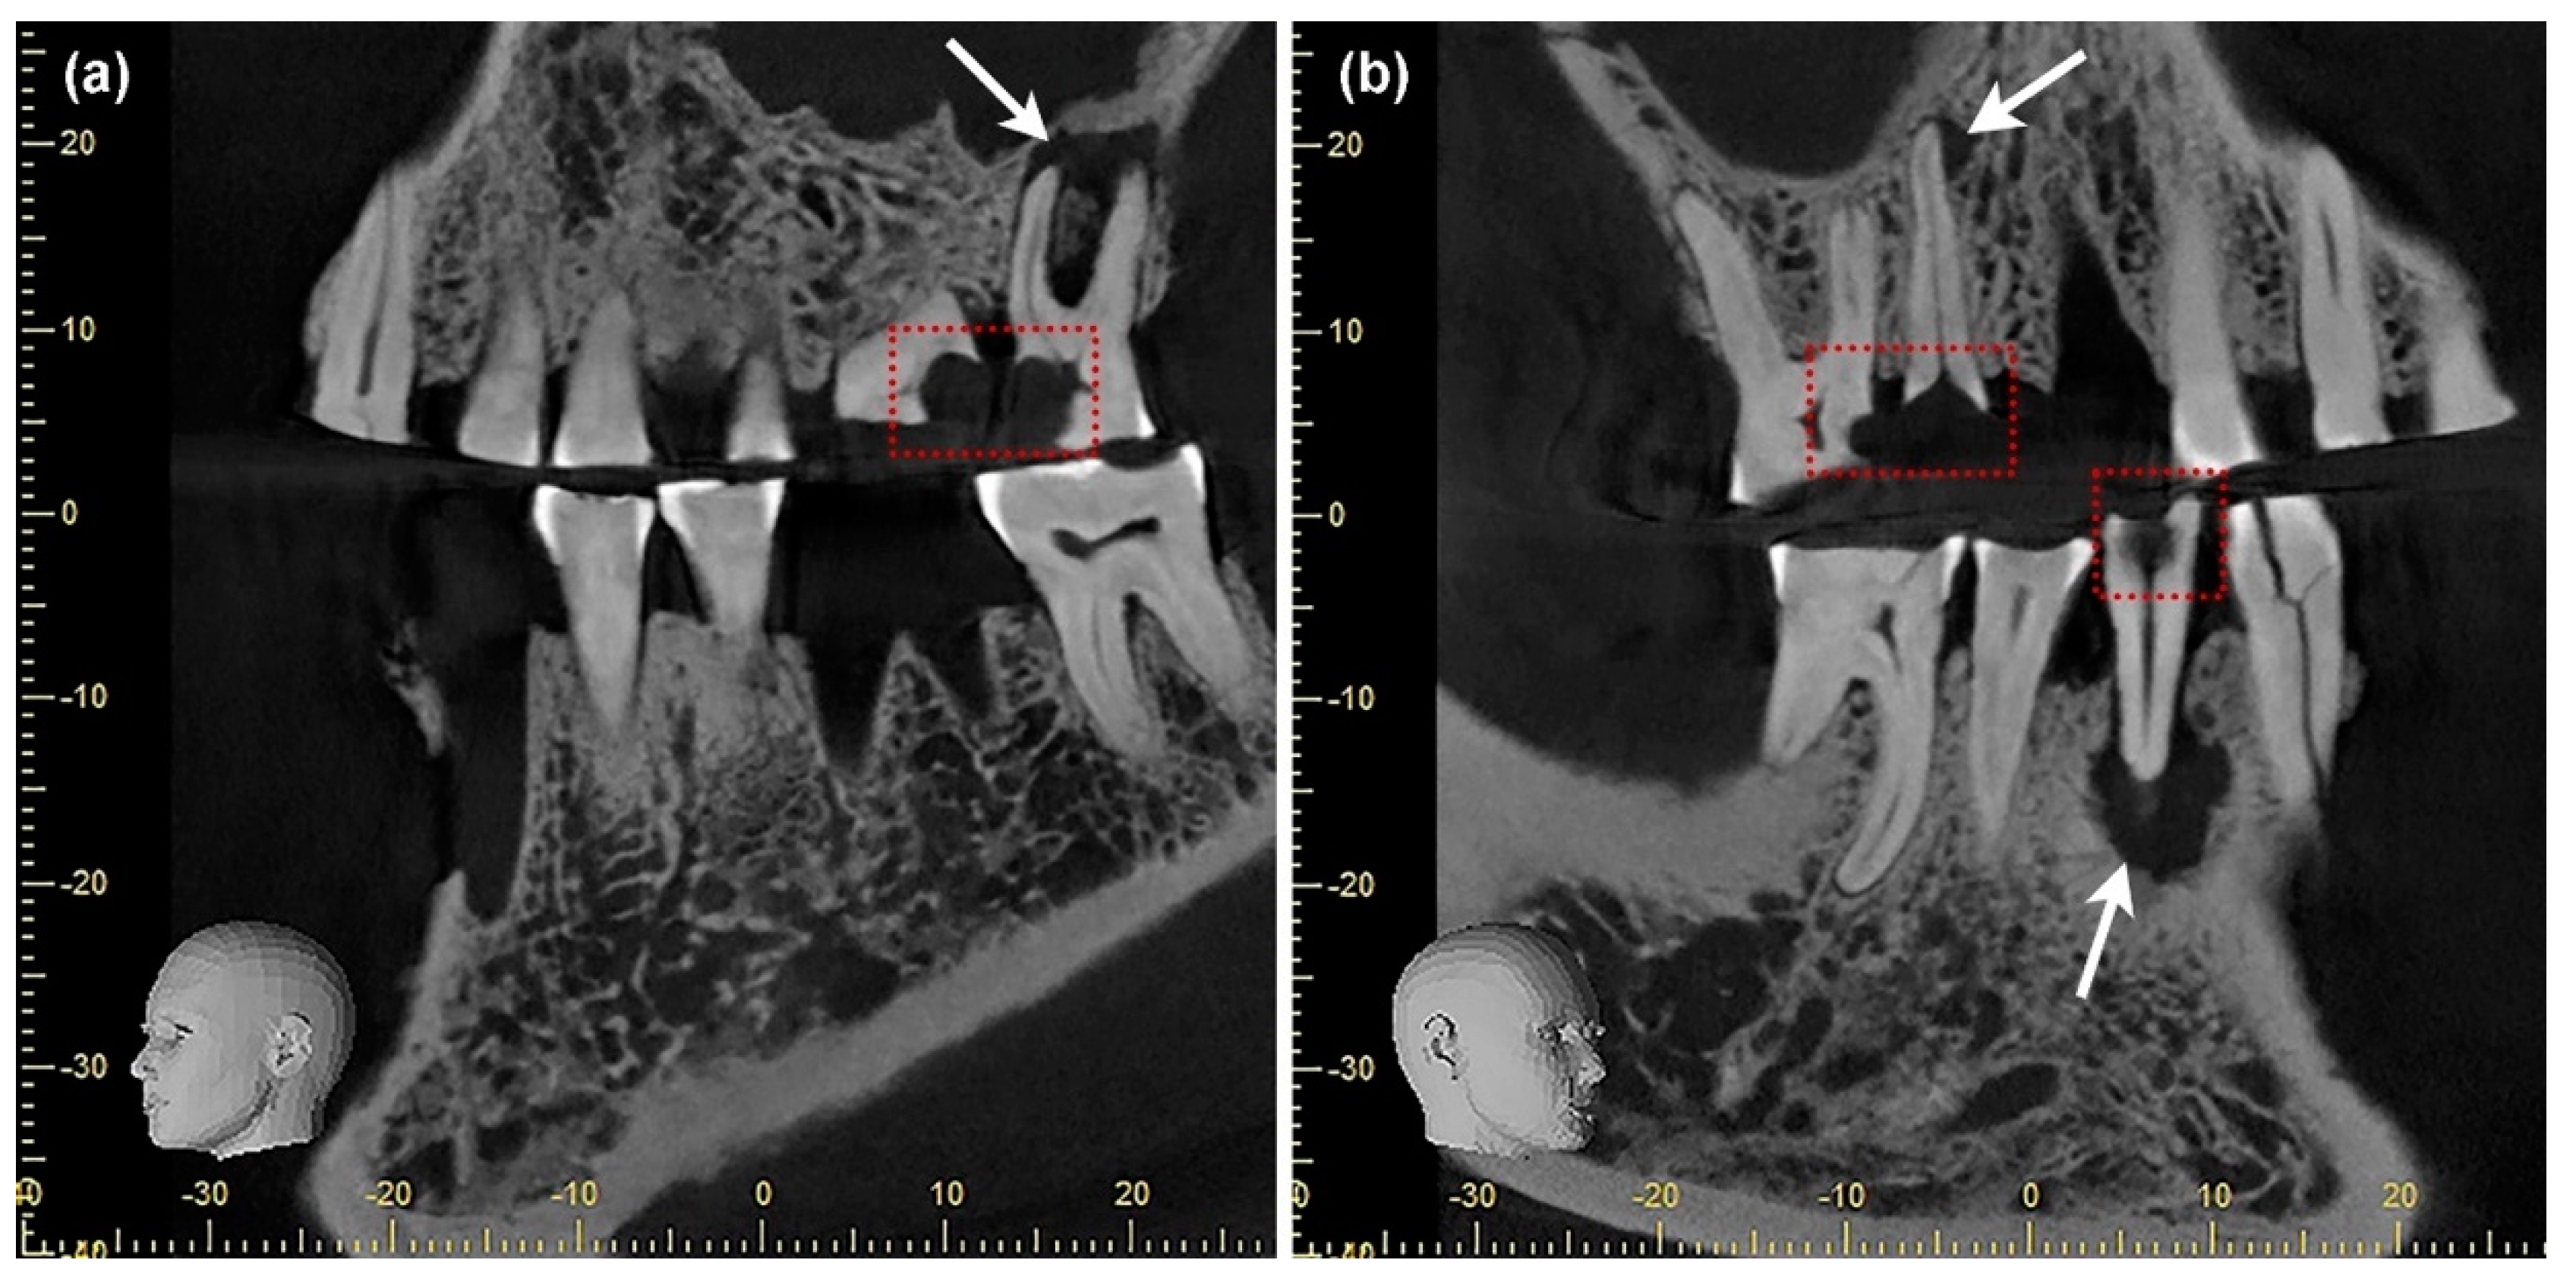

2.2.3. Digital Volume Tomography (DVT)